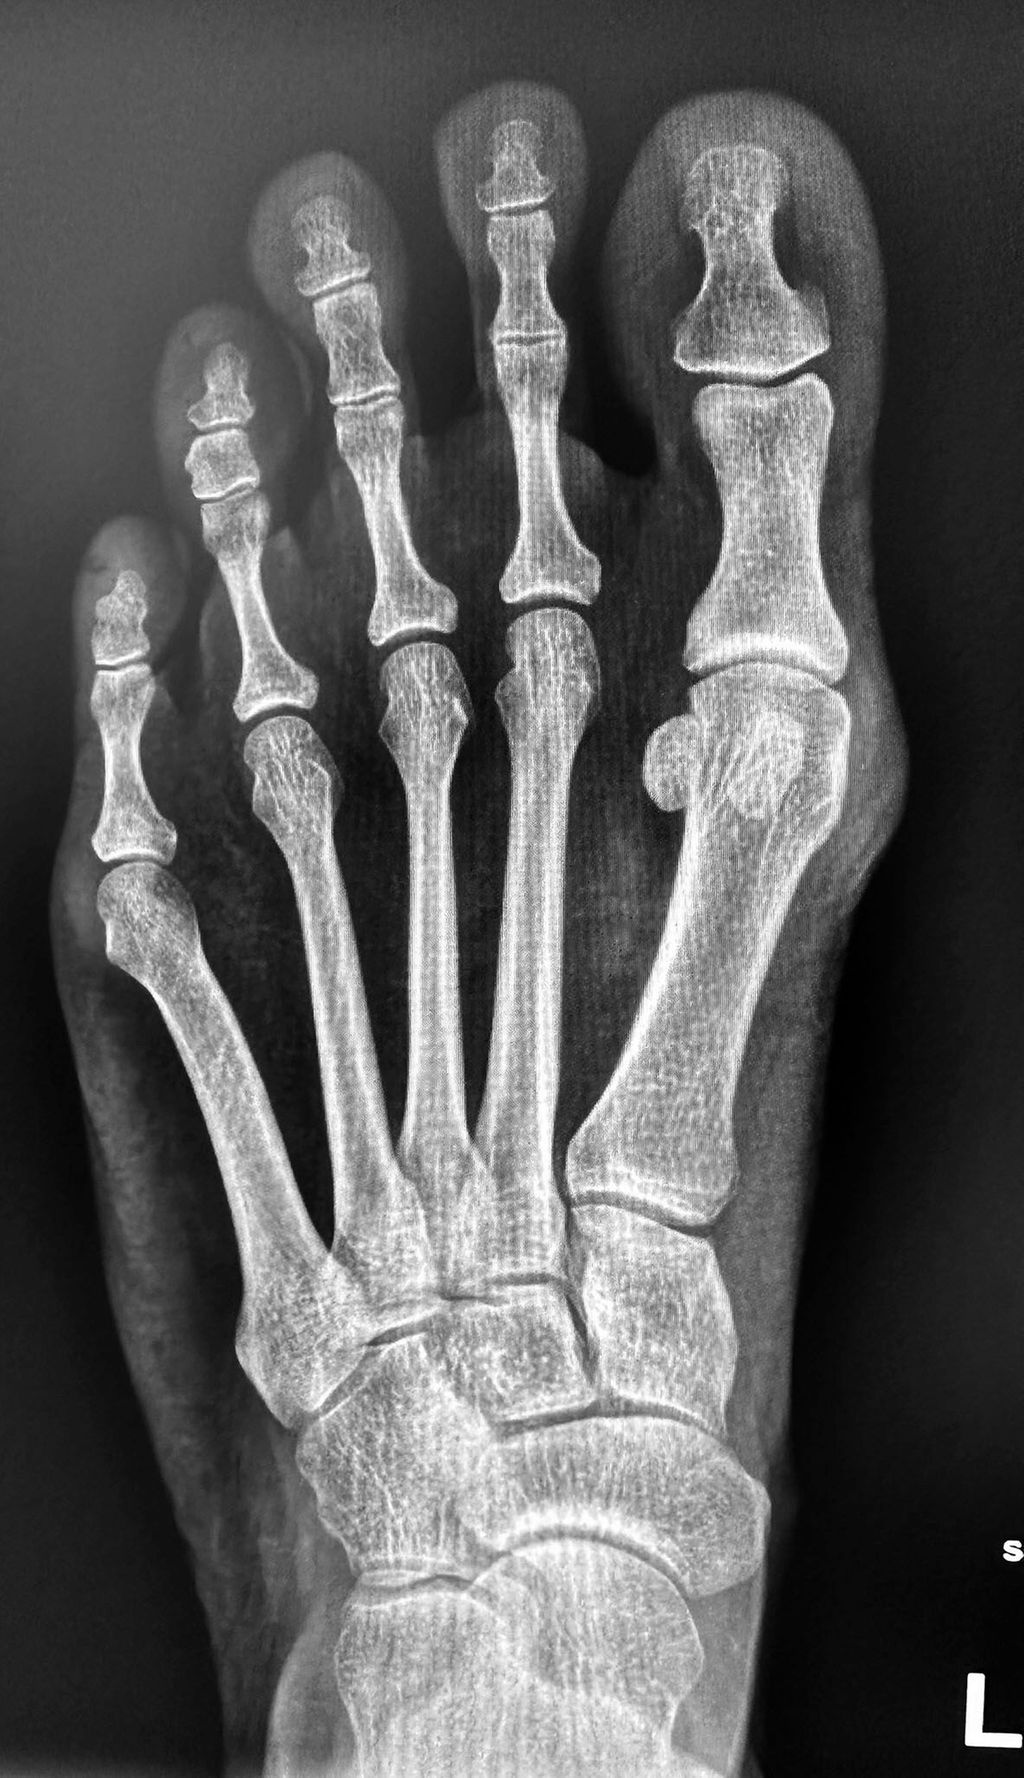

Das Röntgen (Abb. 1) zeigt eine leichte Hallux-valgus-Fehlstellung mit Lateralisation des Sesambeinkomplexes sowie leicht erhöhtem Intermetatarsalwinkel; das Weichteil zeigt eine leichte Schwellneigung am Kopf des Metatarsale I.